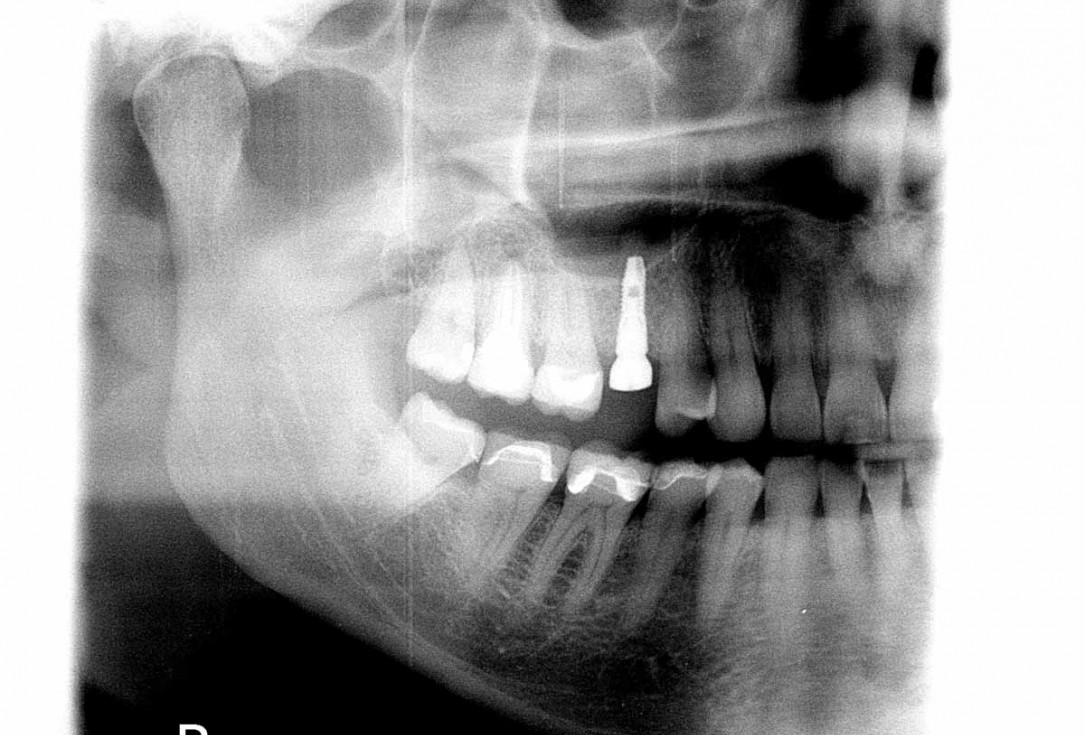

04/06 - Re-entry five months post-operative.Socket preservation with cerabone® - Dr. P. Kämmerer